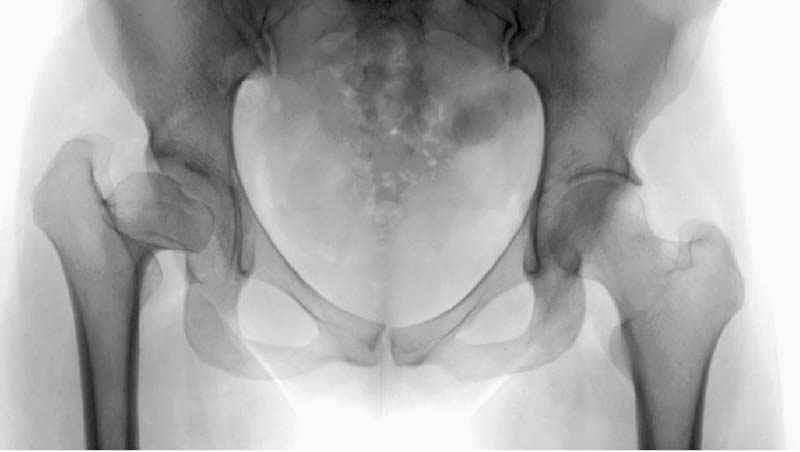

Вашу смелую заявку на новую механику тазобедренного сустава, позволяющую пересмотреть взгляды на патогенез, симптоматику, диагностику, профилактику и лечение заболеваний тазобедренного

сустава, читал со смешанным чувством.

Но, занимаясь с этой патологией, собрал небольшой опыт в лечении остеоартрита, включая: периацетабулярную (ориентационно-корригирующую) остеотомию, и на проксимальной части бедра - valgus, varus, flexion and extension osteotomy и в комбинациях, базирующуюся на авангардных учениях Reinhold Ganz из Bern, на конгруентности сустава и увеличения контактной площади в суставе для уменьшения давления на площади хряща, При Вашем желании можно продемонстрировать результаты наших операций на слайдах.

Кстати, консервативное хирургическое лечение и современное понимание остеоартритов в тазобедренном суставе на том же конгрессе в Москве, где вы и я были участниками, был представлен аудитории во главе с профессором Владимиром Ивановичем Шевцовым. Был проявлен интерес со стороны уважаемых ученых на конгрессе, получил предложение представить сообщение в Кургане в марте 2005 года.